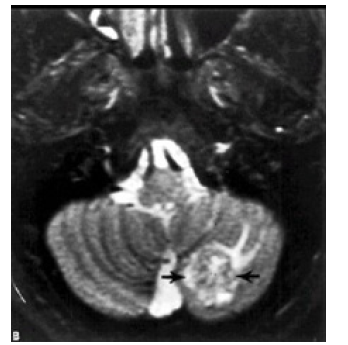

MRI: This was done for only 11 cases according the availability of this study in these hospitals. T1 and T2 studies done for all of those taken the MRI study but Gadolinium contrast study done for only 5 of those cases. (Figure 7& Figure 8 ) Brain MRI T1 and T2 studies